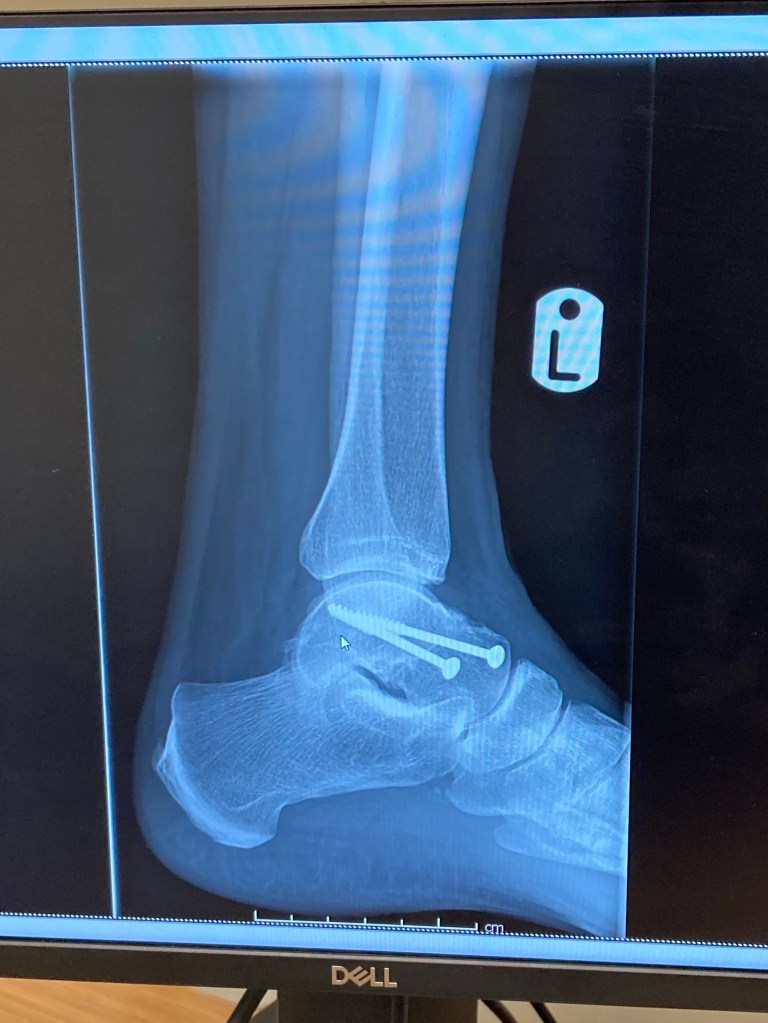

The consultant is very happy with how my ankle has healed. In fact he said it’s the best possible result given the nature of the break. I’ve got a lot more movement that he was expecting. So that’s really good news!